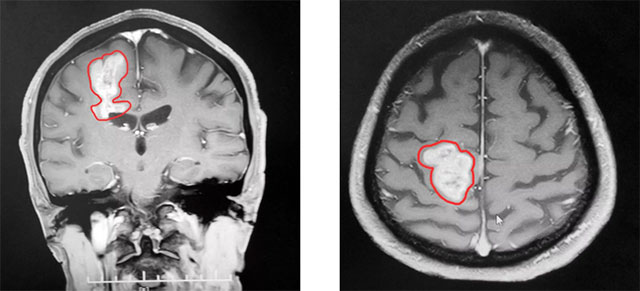

到院時(shí),患者左下肢肌力明顯下降,走路不穩(wěn)。頭顱MRI平掃+增強(qiáng)+MRS+MRSI提示:右側(cè)頂葉占位性病變。根據(jù)患者影像學(xué)檢查及檢驗(yàn)結(jié)果分析,專家認(rèn)為顱內(nèi)腫瘤惡性可能性大,并腫瘤性質(zhì)不明,造成患者生活質(zhì)量下降,應(yīng)盡快行手術(shù)治療,明確病理診斷。

▲ MR顯示腫瘤近4厘米大小

由于腫瘤位于患者右側(cè)中央功能區(qū),術(shù)中可能觸及功能區(qū)及重要血管,手術(shù)極易造成神經(jīng)功能障礙,造成患者術(shù)后肢體癱瘓,語(yǔ)言功能障礙等。術(shù)中術(shù)者對(duì)腫瘤邊界的辨識(shí)、顯微手術(shù)技巧、術(shù)區(qū)止血、周圍腦組織的保護(hù)等任何一點(diǎn)稍有疏忽都可能出現(xiàn)災(zāi)難性后果,手術(shù)難度不言而喻。

李士其教授在助手吳治群博士協(xié)助下,雙極電凝沿腫瘤邊界,在充分保護(hù)神經(jīng)功前的前提下,歷時(shí)三小時(shí),最終2.0*3.0*3.8厘米大的腫瘤被切除。